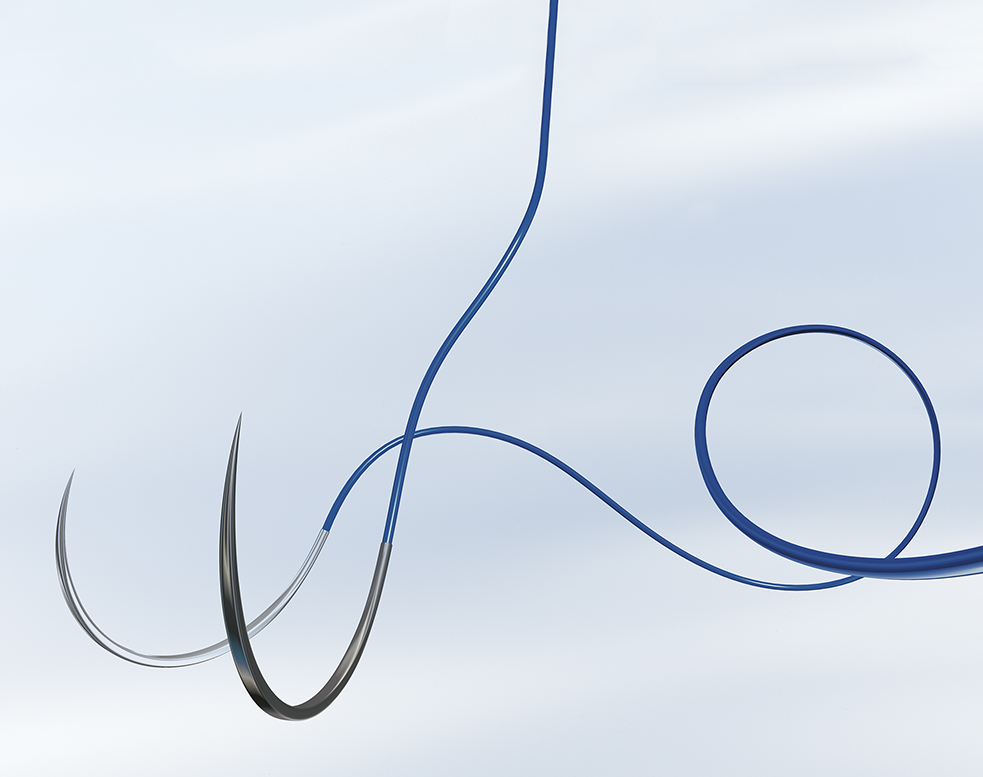

Назва профілю: Нитка хірургічна стерильна з голкою, Поліпропілен і поліетилен, Монофіламентна, 3/0(2,0), довжина нитки, 0,9, м, не розсмоктується, без покриття, 1/2 кола, довжина голки, 22, мм, Колюча, Двох-голкова, без петлі, без насічки, Синій

Тип згину голки

1/2 кола

Кількість голок

Двох-голкова

Довжина голки, міліметр

22

Тип голки

Колюча

OPTILENE, розмір USP 3/0 (2) довжина 90см 2 колючі голки 1/2 кола, довжина (мм) 22 серцево-судинна, пакування RCP

OPTILENE, розмір USP 3/0 (2) довжина 90см 2 колючі голки з коротким ріжучим вістрям, 1/2 кола, довжина (мм) 22 серцево-судинна, пакування RCP

OPTILENE, розмір USP 3/0 (2) довжина 90см 2 колючі голки з коротким ріжучим вістрям, 1/2 кола, довжина (мм) 22 серцево-судинна, пакування RCP

OPTILENE, USP 3/0 (2) довжина 90см 2 колючі голки 1/2 кола, серцево-судинна

OPTILENE, розмір USP 3/0 (2) довжина 90см 2 колючі голки 1/2 кола, довжина (мм) 22 серцево-судинна, пакування RCP